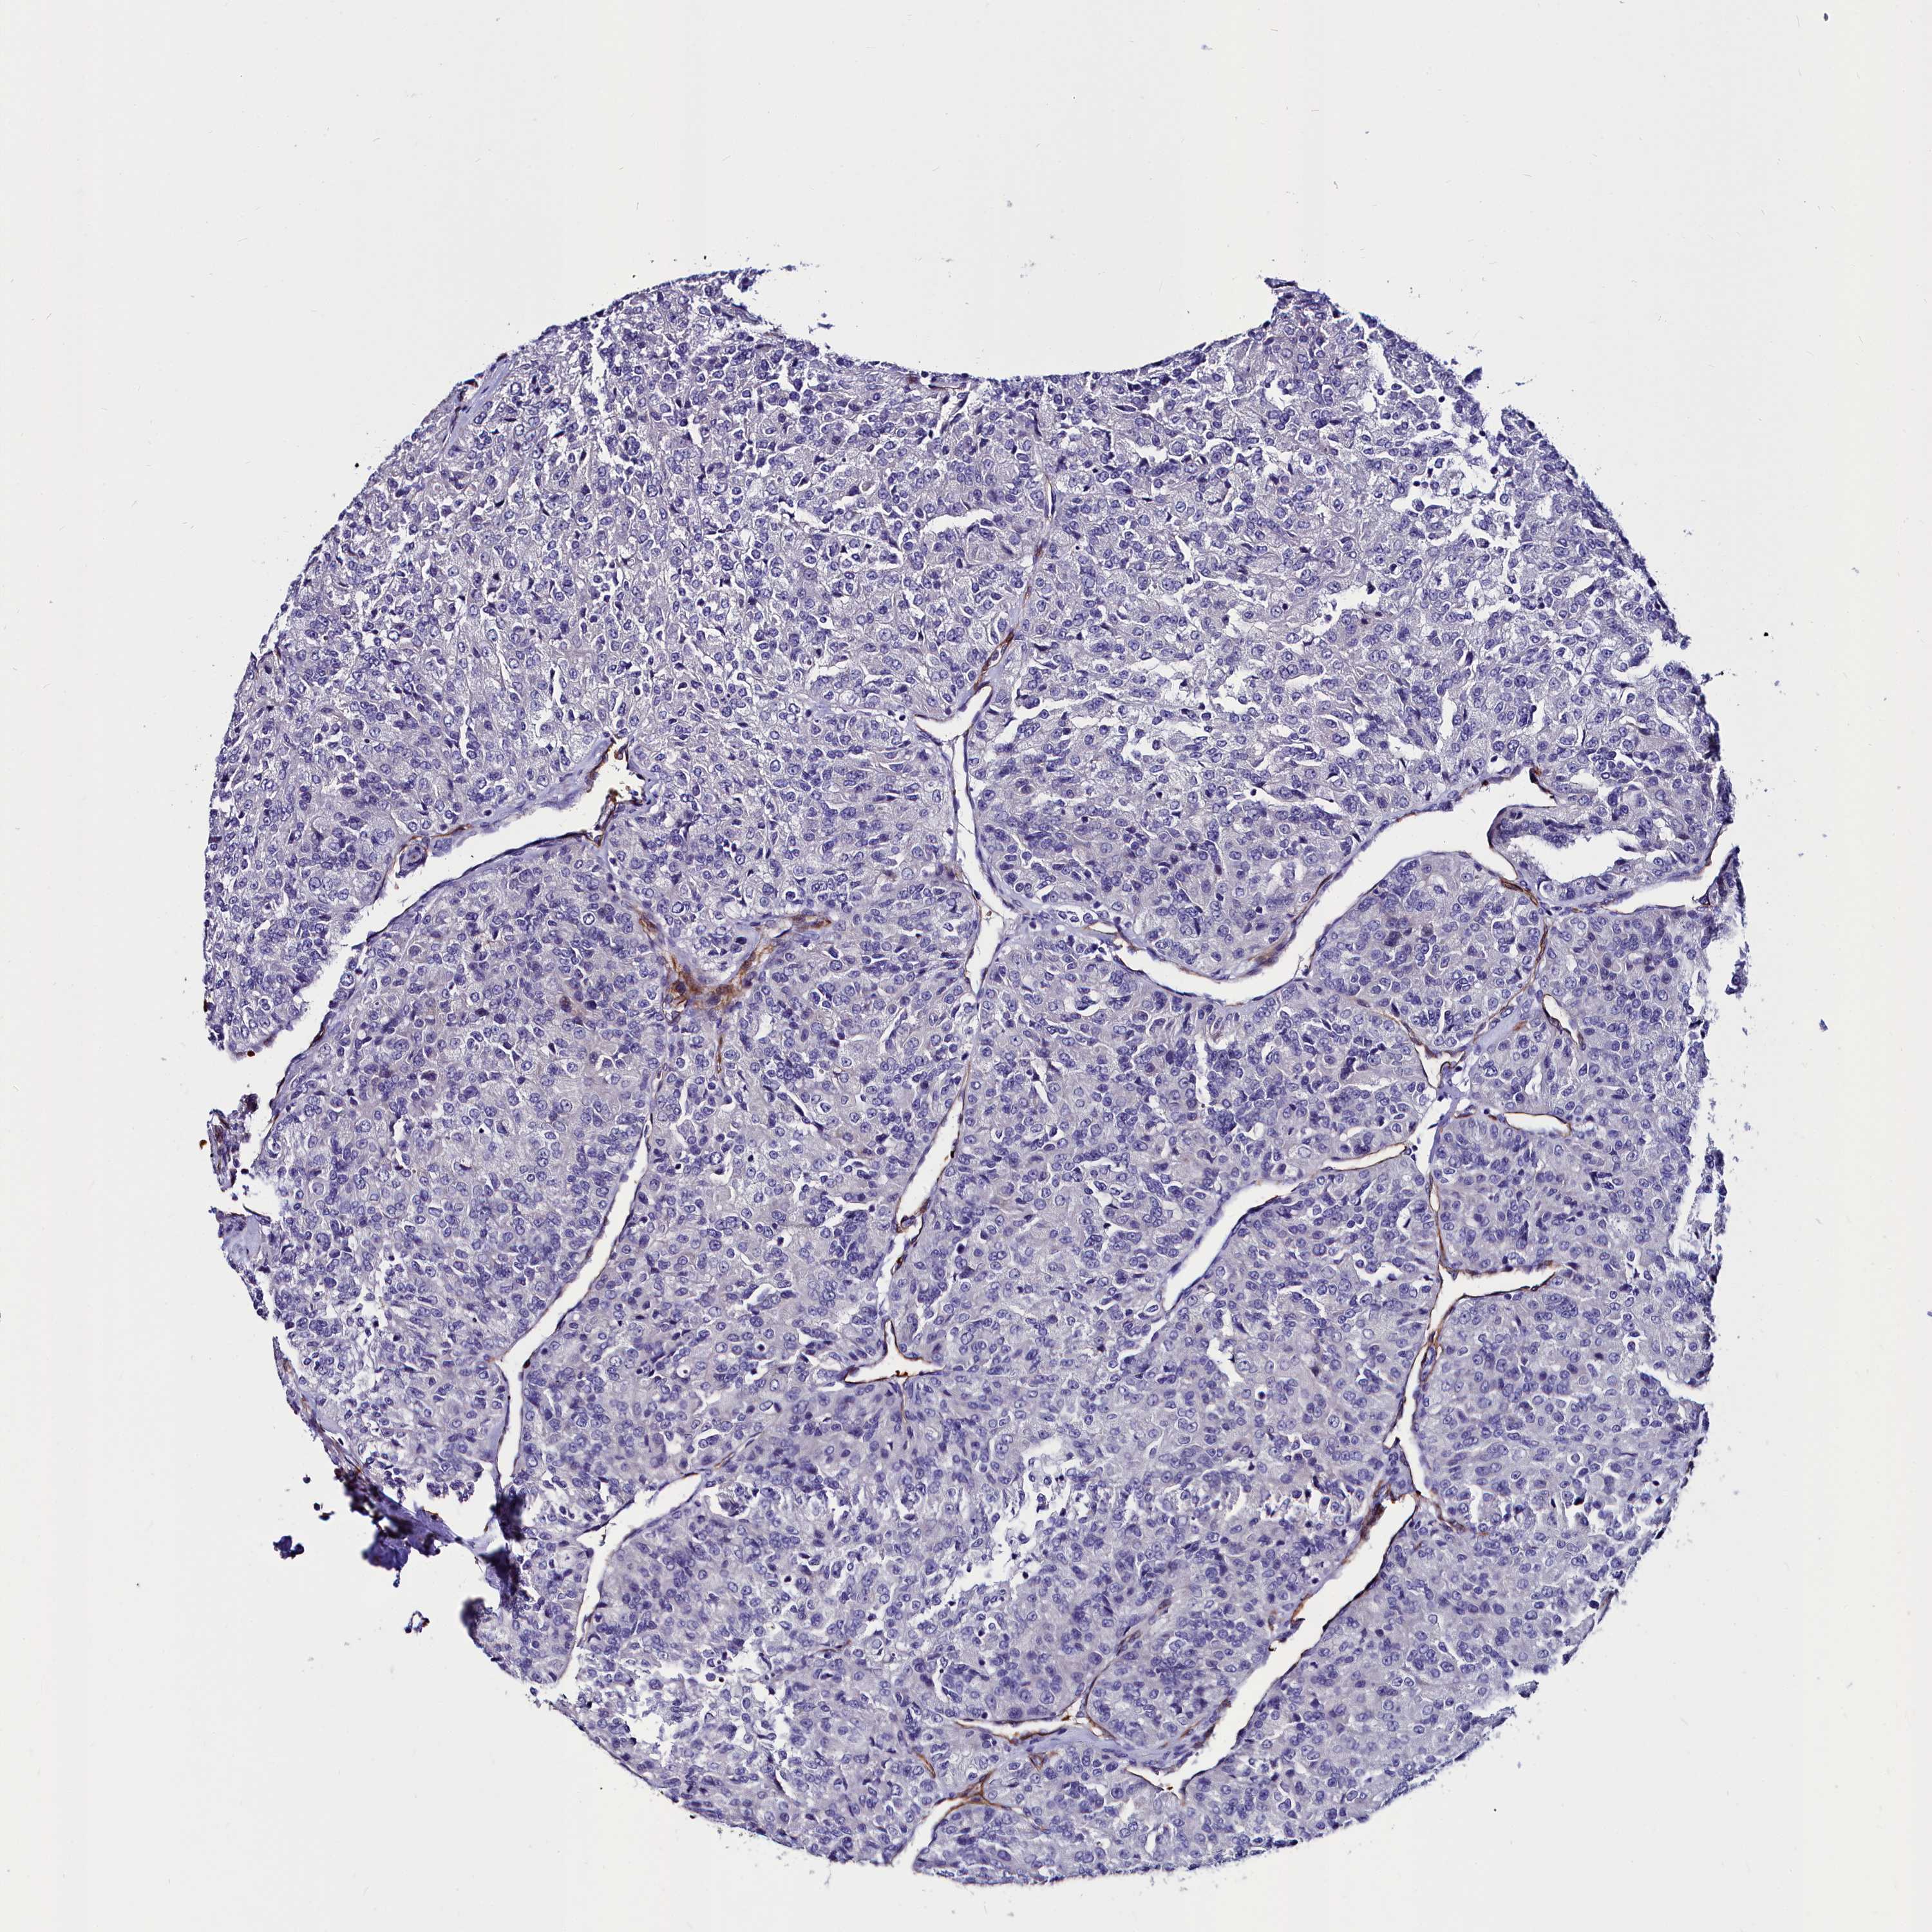

CANCER RENAL CANCER Show tissue menu

KICH TCGA KIRC TCGA KIRC VALIDATION KIRP TCGA PROTEIN RCC CPTAC PROTEIN EXPRESSION